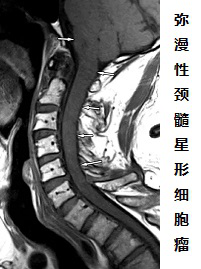

脊髓胶质瘤,顾名思义,即为脊髓内肿瘤,是一种恶性肿瘤,通常生于脊髓内。脊髓胶质瘤与周围生理组织往往没有明显边界,表现为生长浸润性,导致脊髓呈现增粗、肿胀。

脊髓胶质瘤是较常见的脊髓肿瘤,占脊髓髓内肿瘤的80%以上,其年发病率约为0.22人每10万人[1]。脊髓胶质瘤可以是原发性的,多数是转移性的。原发性脊髓肿瘤很少见,通常是良性的。病理上脊髓胶质瘤主要表现为室管膜瘤或星形细胞瘤。室管膜瘤常见于成人,星型细胞瘤是儿童发病率较高的髓内肿瘤。其他还可见血管母细胞瘤、脂肪瘤等。根据肿瘤的解剖位置(肿瘤与脊膜的关系),脊髓胶质瘤分为硬膜内肿瘤和硬膜外肿瘤。生长在脊髓内的的肿瘤称为髓内肿瘤。在椎管内而在脊髓组织外发生的肿瘤称为硬膜内-髓外肿瘤。硬膜外肿瘤占脊髓肿瘤的多数。

脊髓髓内肿瘤(IMSCT)的组织病理学表现主要根据磁共振成像(MRI)表现及特征加以确定。